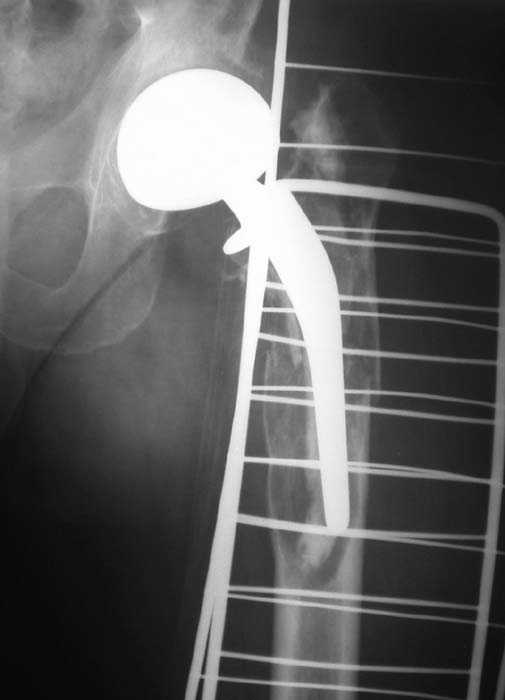

Нет никакого смысла делать операцию в два этапа. С чашкой все понятно - стандартный подход с установкой пресс-фит компонента. На бедре имеет

место перипротезный перелом В3 типа - т.е. перелом вокруг ножки с ее нестабильностью на фоне выраженного остеолиза. Решение - доступ к каналу

через перелом с удалением самой ножки, костного цемента и рубцовых тканей. Установка ножки дистальной фиксации (типа Solution), длину ножки

надо определить по шаблону. Минимальный контакт ножки с интактной костью - 6-8 см. Фрагменты проксмального отдела собираются на ножке

эндопротеза, дефекты костной ткани заполняются чипсами (аллографт) и фиксируются кортикальными аллографтами, уложенными дополнительно по типу

"вязанки хвороста" серкляжом. Мы имеем 8 или 10 подобных наблюдений и результатами довольны.

Абсолютно согласен.Это проверенный путь.Единственное, под Solution надо тщательно удалить цемент из бедра куда встанет дистальная часть ножки.Иначе при установке расколите диафиз бедра.Было поначалу такое у нас.С уважением